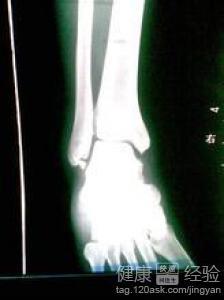

骨折手术,顾名思义,就是通过手术方式治疗骨折。在这个过程中,医生们需要将骨折部位进行复位,然后固定,以确保骨折部位在恢复期间得到充分的休息。

手术过程中,医生们会使用各种工具,如手术刀、骨钻、钢板、螺丝等,对骨折部位进行操作。而这一切,都是在无菌环境下进行的,以确保手术的安全性。